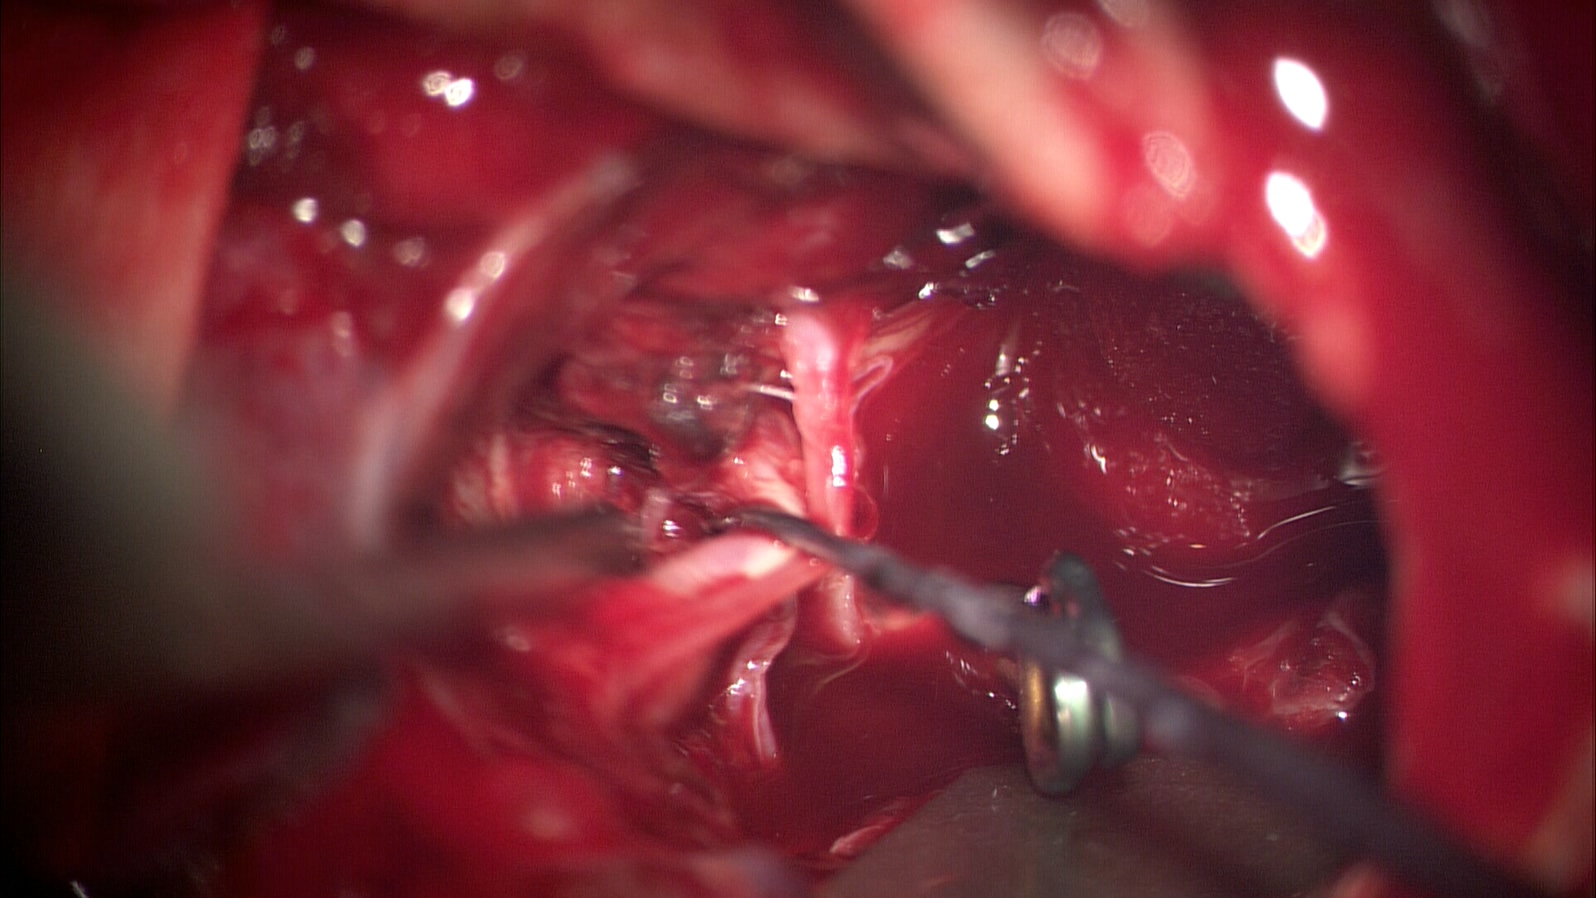

患者老年女性,72岁,昏迷入院。